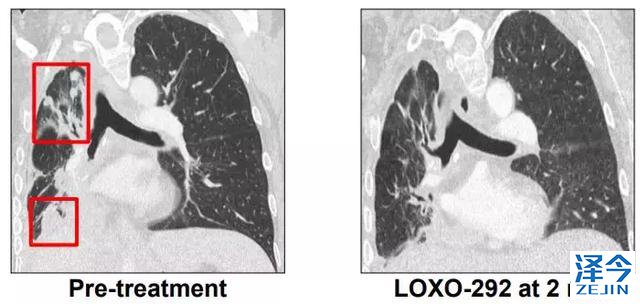

M女士走图无路的情况下接受了基因检测,发现了KIF5B-RET融合,开始接受600 mg BID靶向药 alectinib治疗(PR,7个月),由于脑转移进展增加至900mg BID,后脑转移症状严重,M女士接受了LOXO-292治疗,于是奇迹出现了,治疗两个月后,M女士肺部的病灶明显好转,脑部病灶几乎全部消失!

2018,两款重磅新药给RET基因融合的癌症患者带来春天!